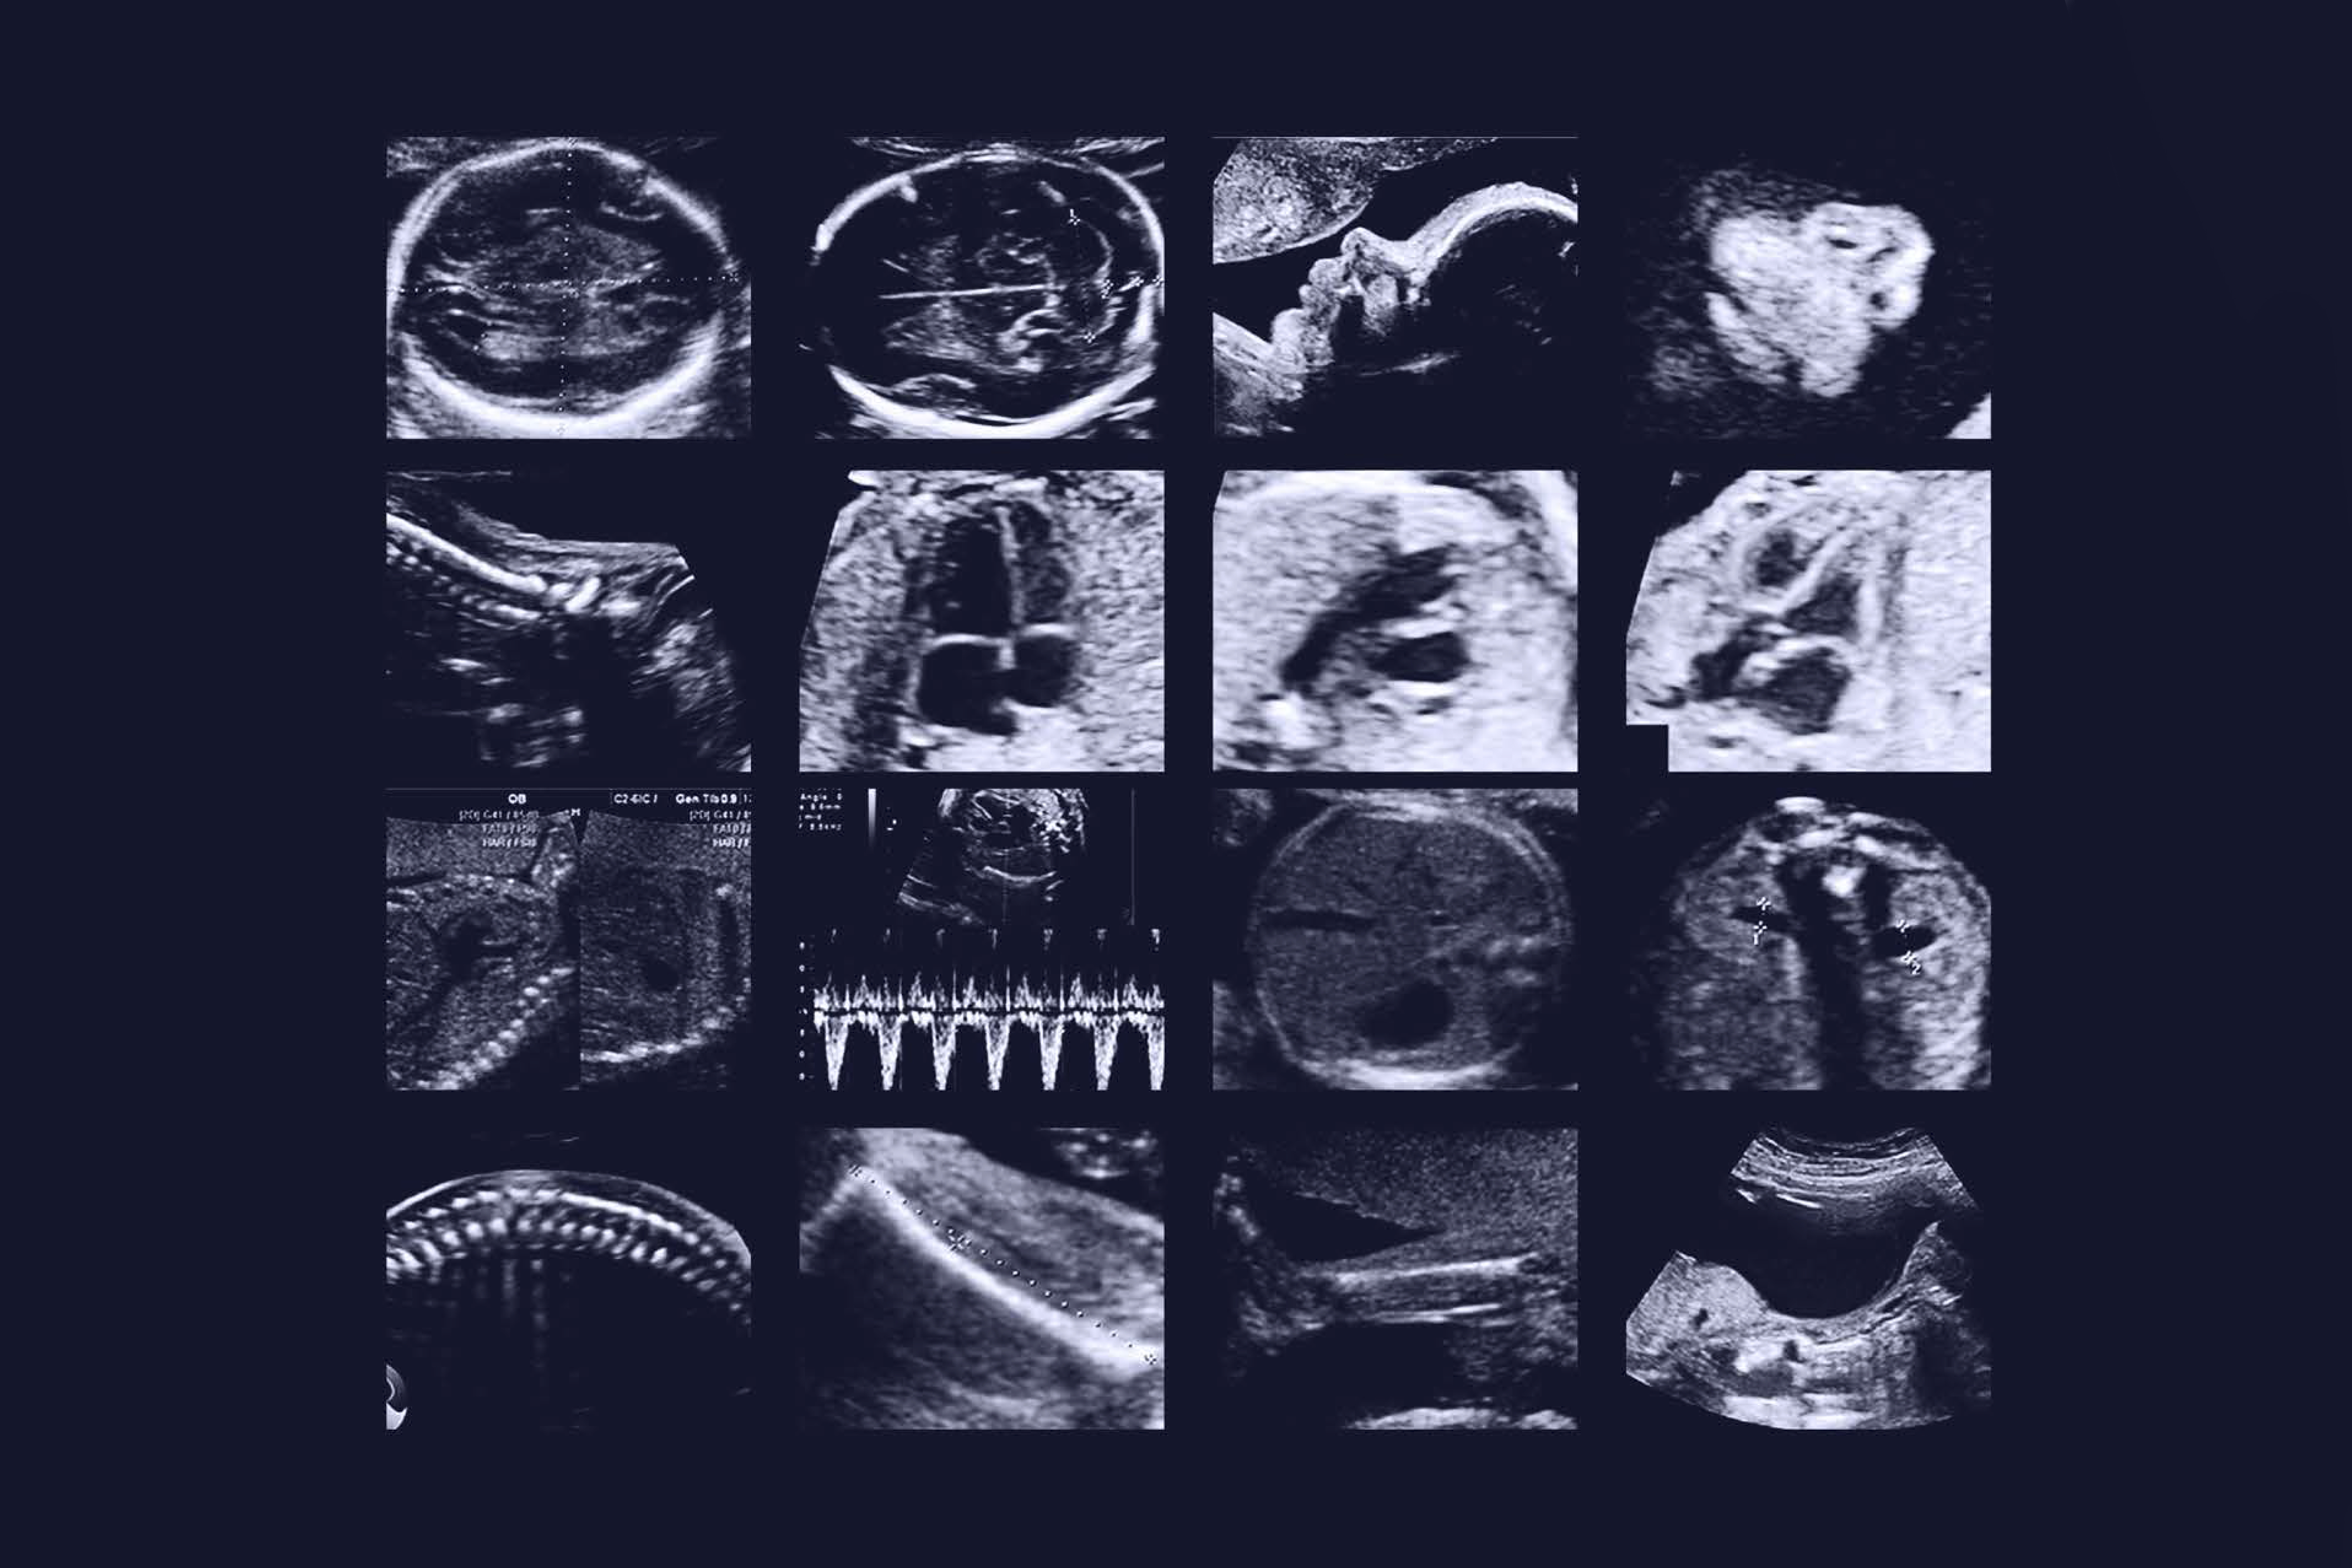

Ecografía detalle anatómico

Existe una ecografía que todas las embarazadas deben hacerse dentro de la semana veinte, veintitrés o veinticuatro, que se conoce como ecografía de nivel tres o ecografía de detalle anatómico. Debe hacerse idealmente entre las 18 a las 22 semanas de embarazo.

Y es donde el médico experto en diagnóstico prenatal valora al bebé desde la cabeza empezando por el cerebro, para ver cómo están los ventrículos, descartar el aumento del líquido cefalorraquídeo que se llama ventriculomegalia o hidrocefalia, ver el cerebelo, ver la columna, descartar espina bífida.

También se valora el abdomen, donde la inserción del cordón umbilical debe estar de determinada manera para descartar una cosa que se llama onfalocele, o la evisceración de los intestinos en el feto que se llama gastrosquisis y determinar que la pared abdominal esté intacta, que el hígado esté intacto, que los riñones estén de tamaño normal sin evidencia de quistes o de masas tumorales, porque puede haber quistes en los riñones o una situación que vemos muy frecuentemente que se llama ectasia renal, que es una dilatación de la pelvis del riñón que generalmente sucede por el reflujo de la orina, desde la vejiga hacia arriba porque el bebé no puede vencer la barrera en el líquido amniótico donde está y se devuelve un poco la orina por reflujo. Es un evento fisiológico, no es anatómico y la mayoría de los bebés al nacer ya no tienen lo que llamamos ectasia renal.

También valoramos el corazón, debe tener sus cuatro cavidades simétricas, las dos aurículas, los dos ventrículos, los tractos de salida de la parte derecha del corazón, de la parte izquierda del corazón, el ritmo cardíaco, la apertura de las válvulas del corazón (mitral, tricúspide, aórtica y pulmonar), todo eso lo valoramos en la ecografía de detalle anatómico, valoramos también los pulmones porque también puede haber patología en los pulmones. Podemos ver su cara, para ver los labios y descartar fisuras del labio y del paladar

Lógicamente en el nivel tres o en la ecografía estructural debemos ver los dos miembros superiores, las manitos, que tenga sus deditos completos y los miembros inferiores igual, que estén en la posición correcta, porque hay una cosa que se llama pie equinovaro, que es los piecitos metidos hacia adentro, que lo vemos con alguna frecuencia, uno ve por hay unos cuatro o cinco casos al año de pie equinovaro donde vemos los pies angulados o metidos hacia adentro.

También debemos observar la anatomía del cordón umbilical donde debemos encontrar 2 arterias y una vena umbilical, ademas debemos observar su insercion en la pared abdominal del bebe y la insercion en la placenta. Cuando observamos solo una arteria umbilical debemos hacer un seguimiento mas estricto al crecimiento fetal para descartar bebes pequeños.

Valoramos la placenta, en fin en una ecografía que dura aproximadamente entre veinte a treinta minutos, debemos valorar de pies a cabeza la anatomía del bebé y poderle decir a los padres que la anatomía de su bebé se desarrollo normalmente y el niño no tiene ningún defecto visible por ecografía. Debemos recalcar que la ecografía tiene hasta un 80% de posibilidad de detectar alteraciones mayores de los bebés. No se puede encontrar el 100% de los defectos por dicho exámen. Es una evaluación que todas las mujeres embarazadas se deben realizar entre las 18 a 22 semanas.